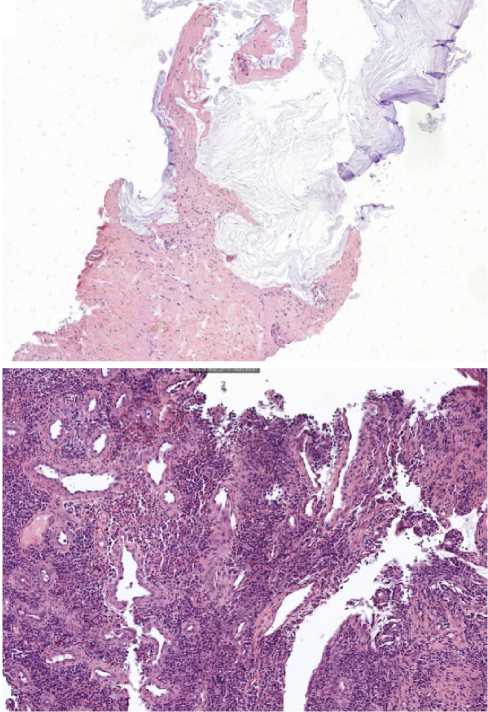

Помимо этого, пациенту проведена видеоколоноскопия: в просвете верхнеампулярного отдела прямой кишки сохраняется стенозирующая опухоль (рис. 11). По результатам гистологического исследования биоптатов опухолевых клеток не выявлено, фрагменты грануляционной ткани с участками слизистой оболочки толстой кишки (рис. 12).

Рис. 12. Результаты морфологического исследования: а - препарат печени (×200), б-препарат кишки (×20) на фоне 14 введений иммунотерапии пембролизумабом у пациента 38 лет с диагнозом метастатический колоректальный рак с признаками микросателлитной нестабильности; опухолевых клеток не выявлено

Fig. 12. Results of morphological examination: a - liver preparation (×200), b - intestine preparation (×20) against the background of 14 infusions of pembrolizumab immunotherapy in a 38-year-old patient diagnosed with metastatic MSI-H colorectal cancer; tumor cells were not detected